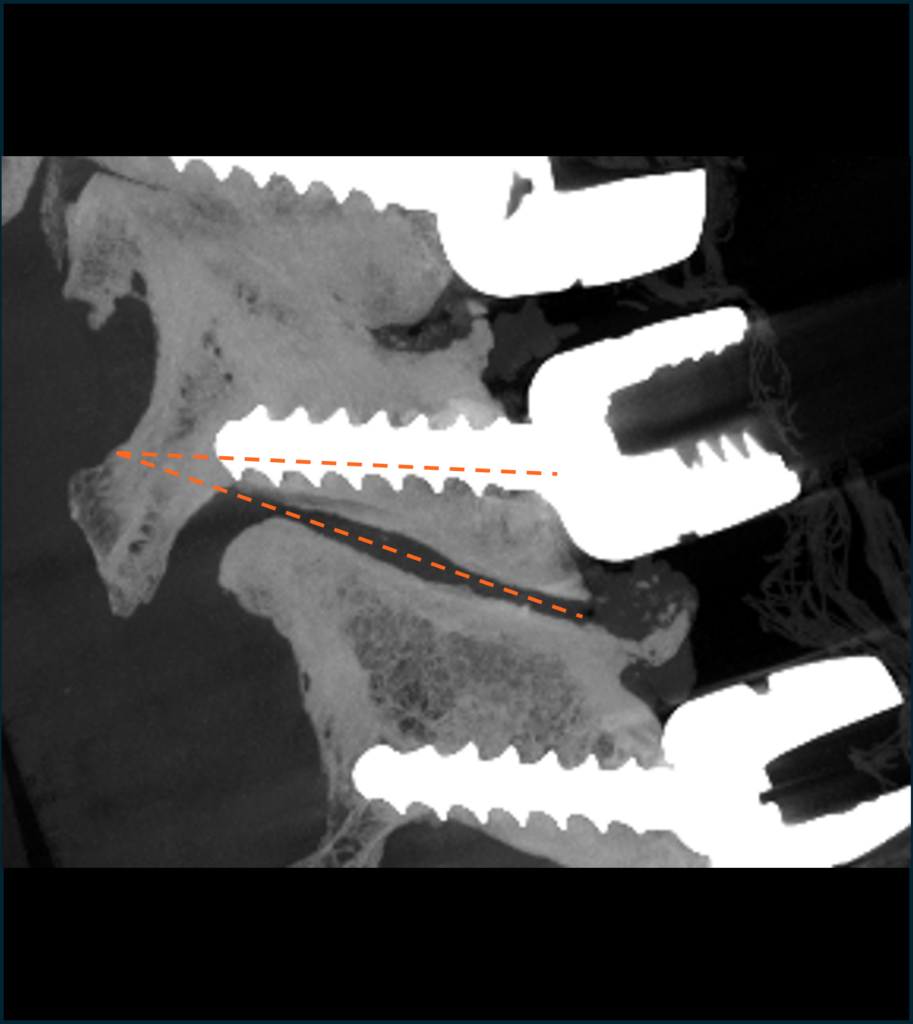

Improved screw trajectory

Reduced rates of screw breach

Sagittal screw angle measured relative to inferior facet joint

Freehand

Facet Fusion